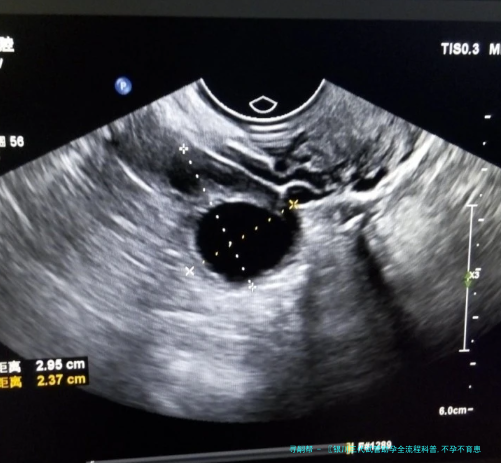

促排卵阶段意在让女性卵巢内多个卵泡同时发育。通过注射荷尔蒙刺激卵巢发生还要多卵子,提高获卵子数量和受孕几率。

医生会陆续监测卵泡的大小和数量,认为最完美取卵时间。这个过程通常须要15-二十天,要求患者严格依照医嘱协同治疗。

当卵泡发育成熟后,需要打破卵针,然后在36小时左右安排取卵手术。促排卵期间,病患应该多补充蛋白质,多吃富含有量多纤维的清爽蔬菜水果。

取卵手术通常在静脉下进行,患者不会感应疼痛。医生在超声波引导下,用细针将卵子抽拿出来,全部过程安全可控。